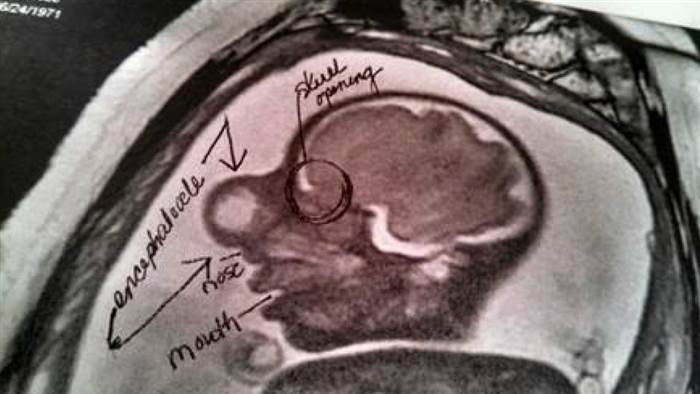

Analisi più approfondite hanno svelato che la diagnosi era più grave: si trattava di encefalocele.

La testa del piccolo non si era chiusa in modo appropriato consentendo ad alcune parti del cervello di sfuggire nello spazio tra gli occhi e formarsi come un sacco che ricopriva il volto del bimbo.

Zackary stava bene, ma l’enorme sacco sul volto gli comprimeva le cavità nasali.

Una piccola imbracatura gli teneva sollevato il sacco dal naso e dalla bocca in attesa dell’operazione che avrebbe potuto risolvere il suo problema.